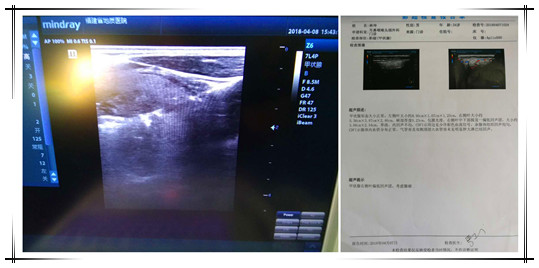

患者林某某、福州仓山籍、男性、34岁,以发现右颈部肿物1月余为主诉入院,甲状腺彩超示:右侧中下部探及一偏低回声团,大小约3.88cm x 2.54cm。经过术前周密检查,决定实施低温等离子消融术切除甲状腺肿瘤。消融治疗时间很短,约30分钟,术后病人即可下地行走、起居自如,第二天便可出院,患者林先生自己都不敢相信小小一根针可以获得如此惊人的效果。